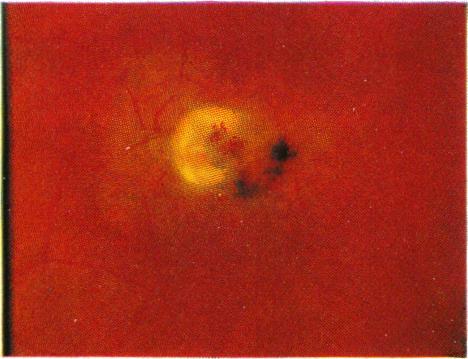

Braley A E, Spivey B E

Trans Am Ophthalmol Soc. 1963;61:339-71.